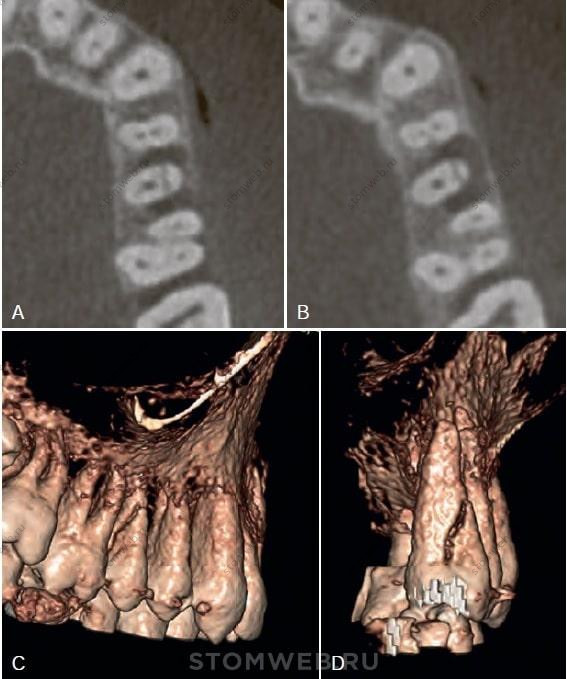

РИС. 21-7 Диагональный перелом зуба. Правый верхний второй премоляр с мезиодистальным переломом коронковой части. А,В) На двух горизонтальных срезах КЛКТ виден мезиодистальный перелом с сопутствующей потерей костной ткани в апроксимальных участках. Ближе к коронке деструкция кости наблюдается щечно и мезиально (А). Более апикально потеря костной ткани присутствует медиально, щечно и дистально (В). С,D) На трехмерном изображении отчетливо видна конфигурация перелома, которая свидетельствует о невозможности сохранения зуба. Объем деструкции костной ткани и широкий просвет линии перелома свидетельствуют о длительности поражения, при которой резорбция кости привела к расхождению фрагментов, заметному на КЛКТ. Не похоже, чтобы такая выраженность линии перелома могла присутствовать на ранней стадии его формирования.